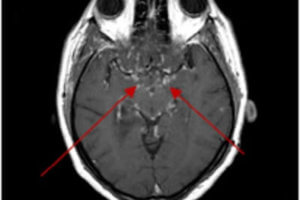

Neurosarcoid

Sarcoidosis is a systemic inflammatory condition with a specific pathology – non caseating (unlike TB) granulomas. The condition affects the lungs , bones and brain. Neurosarcoid occurs in about 5-10% of patients... Read more »